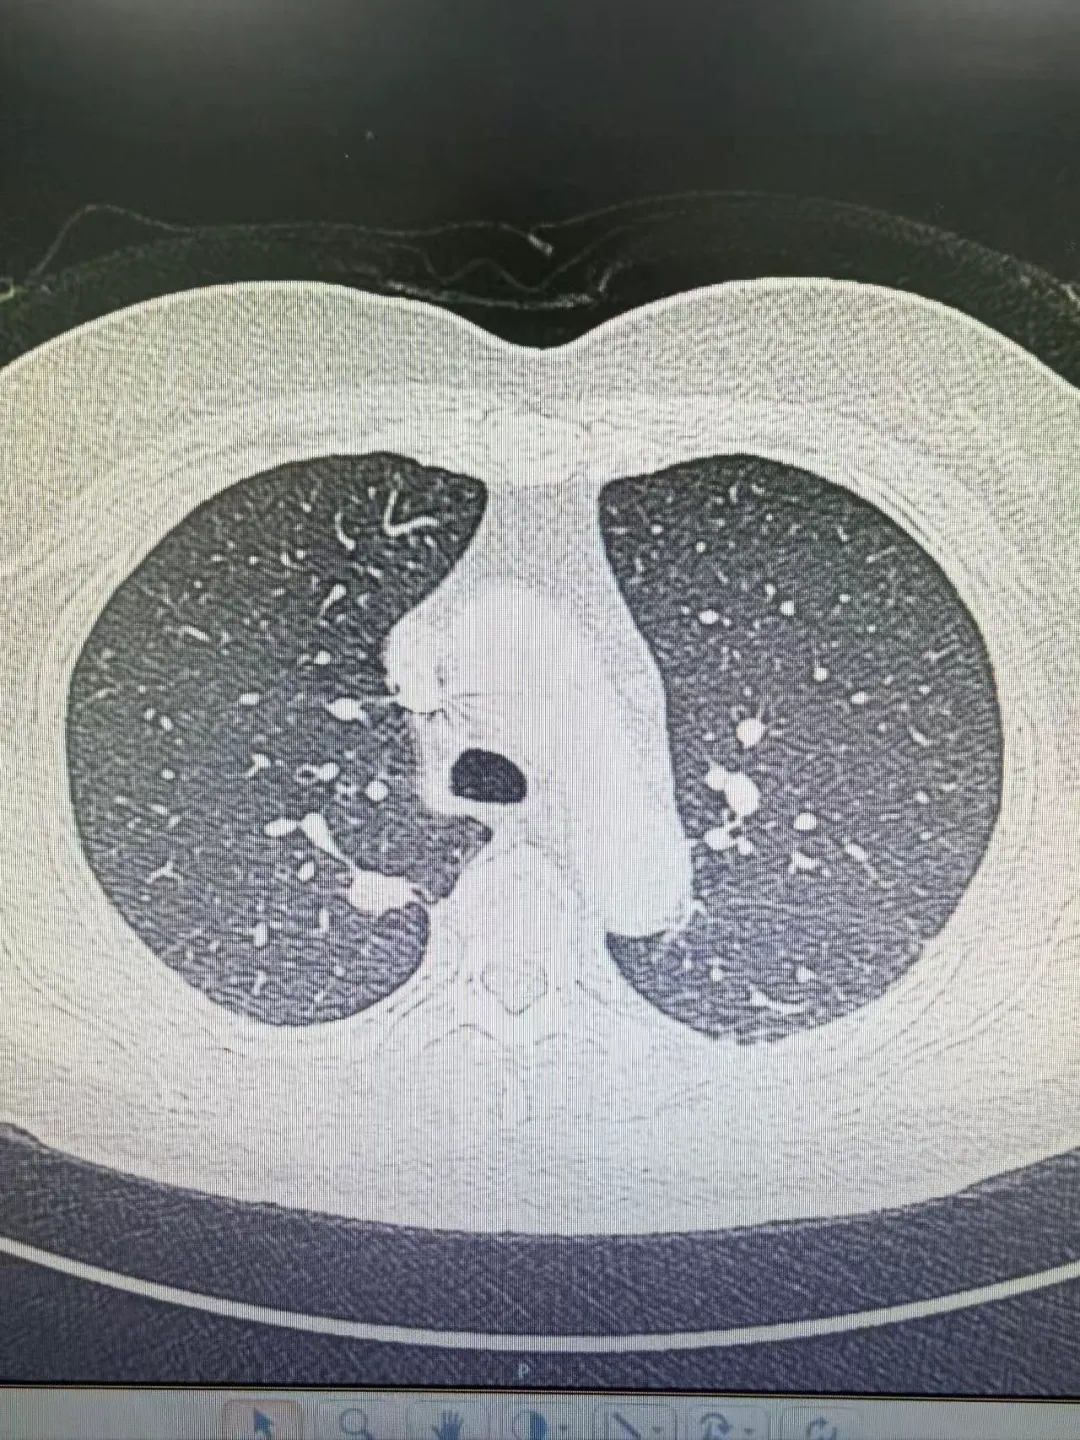

病例2:

患者伦某,因胸闷、憋气1月就诊于我院老年医学科,行胸部CT检查示右肺上叶后端结节,考虑恶性可能性大,随转入我科。在拟上手术前一天,经张振江主任阅读病史及综合分析后考虑结节存在良性可能,果断终止手术,后行穿刺诊疗,确诊为良性结节。随访至今略有缩小。

2025.06.27 胸部CT

2026.02.03 胸部CT